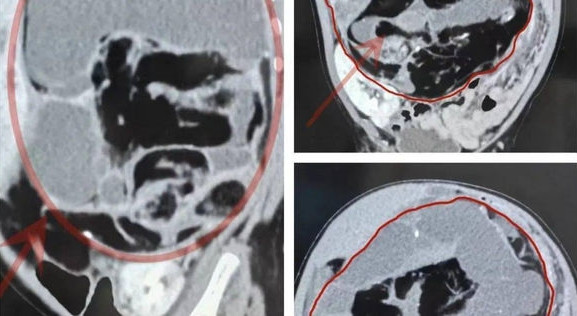

| 80% toàn bộ khoang bụng của Miêu Miêu bị che phủ bởi khối u, toàn bộ cơ quan nội tạng trong khoang bụng bị di lệch, không đúng vị trí. |

Rachael lần đầu tiên bị ốm khi mới 24 giờ tuổi. Kết quả chụp cắt lớp cho thấy cô bị bệnh u xơ toàn thân bẩm sinh dạng nặng nhất. Rối loạn hiếm gặp khiến các khối u lành tính phát triển ở da, cơ, xương và các cơ quan.

Katie chia sẻ: “Chúng tôi chưa bao giờ nghe nói về căn bệnh đó trước đây. Các bác sĩ nói các khối u nằm trên mọi cơ quan trong cơ thể con tôi. Một số u rất nhỏ nhưng một số khác thì lớn, lên đến vài cm. Các khối u ở tim còn gây viêm”.